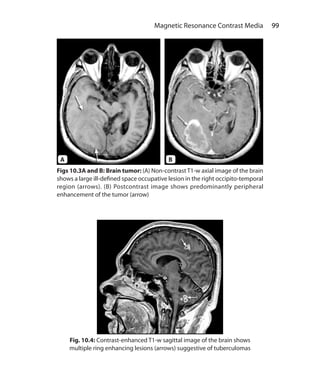

Chapter 10.  Magnetic Resonance Contrast Media	 91

Role of Contrast in MRI	 98

Chapter 12.  Principles of Interpretation: Body Imaging	 115

Sequences		 115